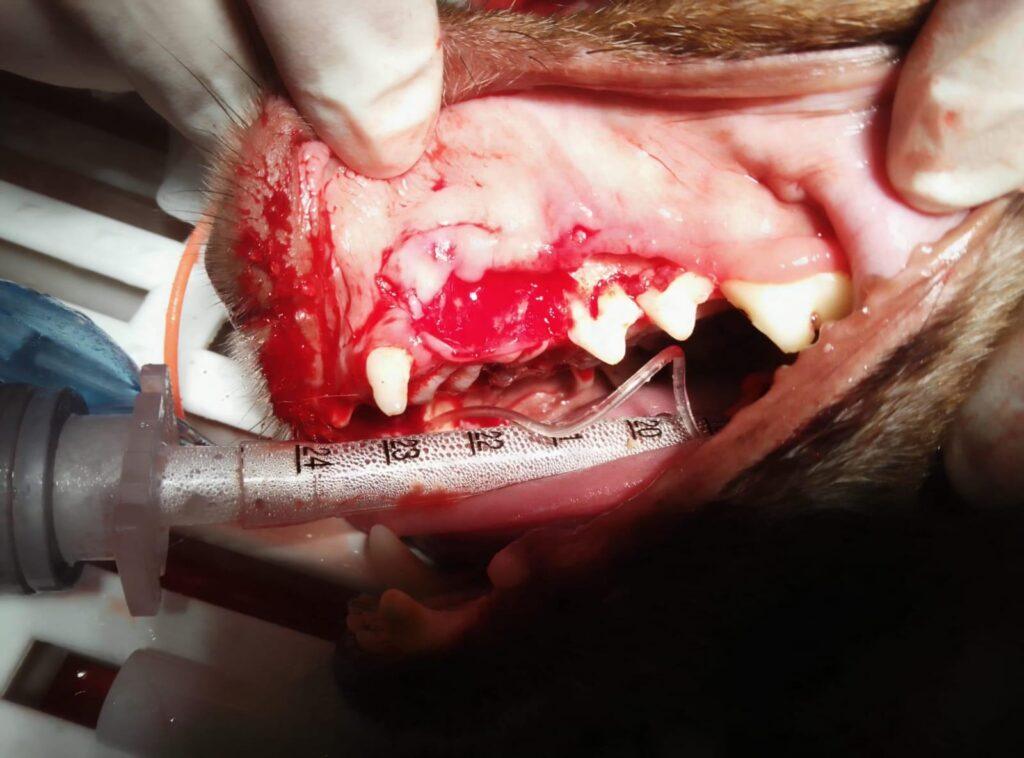

Liebe PfotenFreunde, Mirto hat seine Zahn-OP erfolgreich über die Bühne gebracht. Die OP war sehr aufwendig. Zuerst wurde eine Zahnreinigung gemacht. Danach wurden dem kleinen Mann 12 Zähne gezogen, ein Zahn war gebrochen und musste heraus operiert werden. Außerdem stellte man bei der OP fest, dass Mirto eine starke Parodontis hat, die man bei der Gelegenheit auch gleich mit behandelt hat.

Mirto geht es gut und er kann nun endlich schmerzfrei fressen.